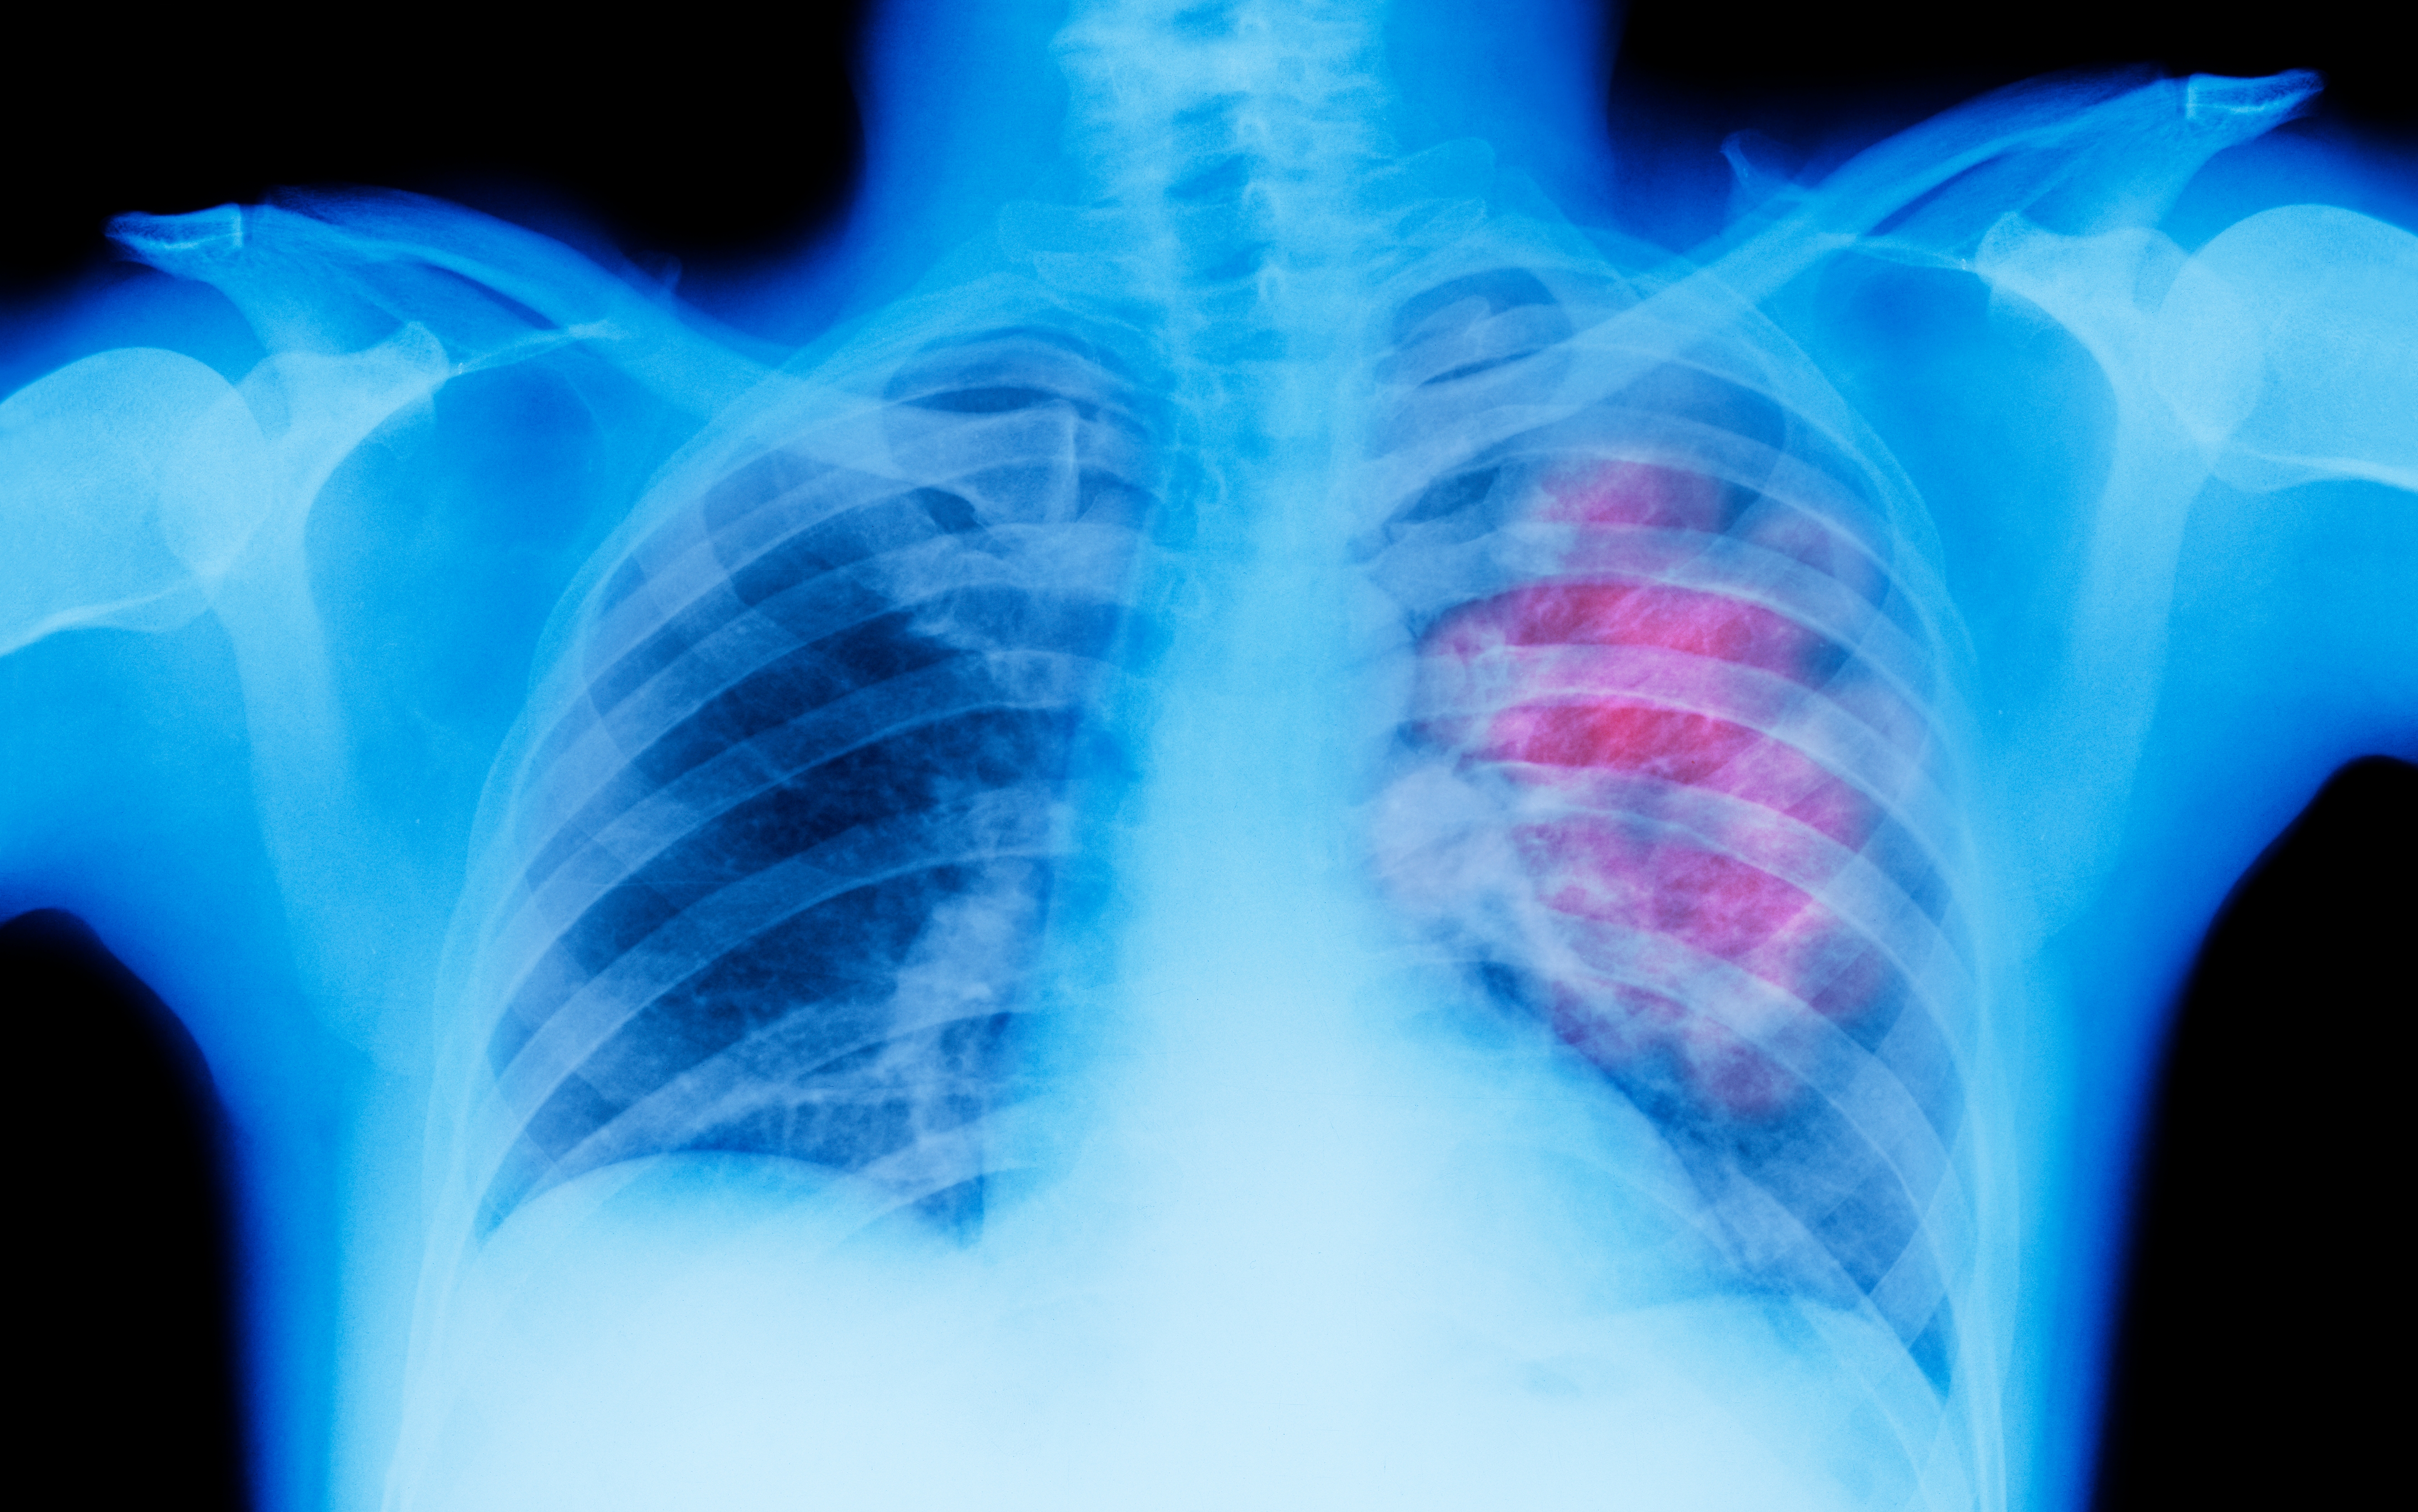

20.And finally: “We don’t know why people get certain kinds of cancer. My aunt had lung cancer (which was thankfully caught and treated early) even though she never smoked, and no one knew exactly why.”